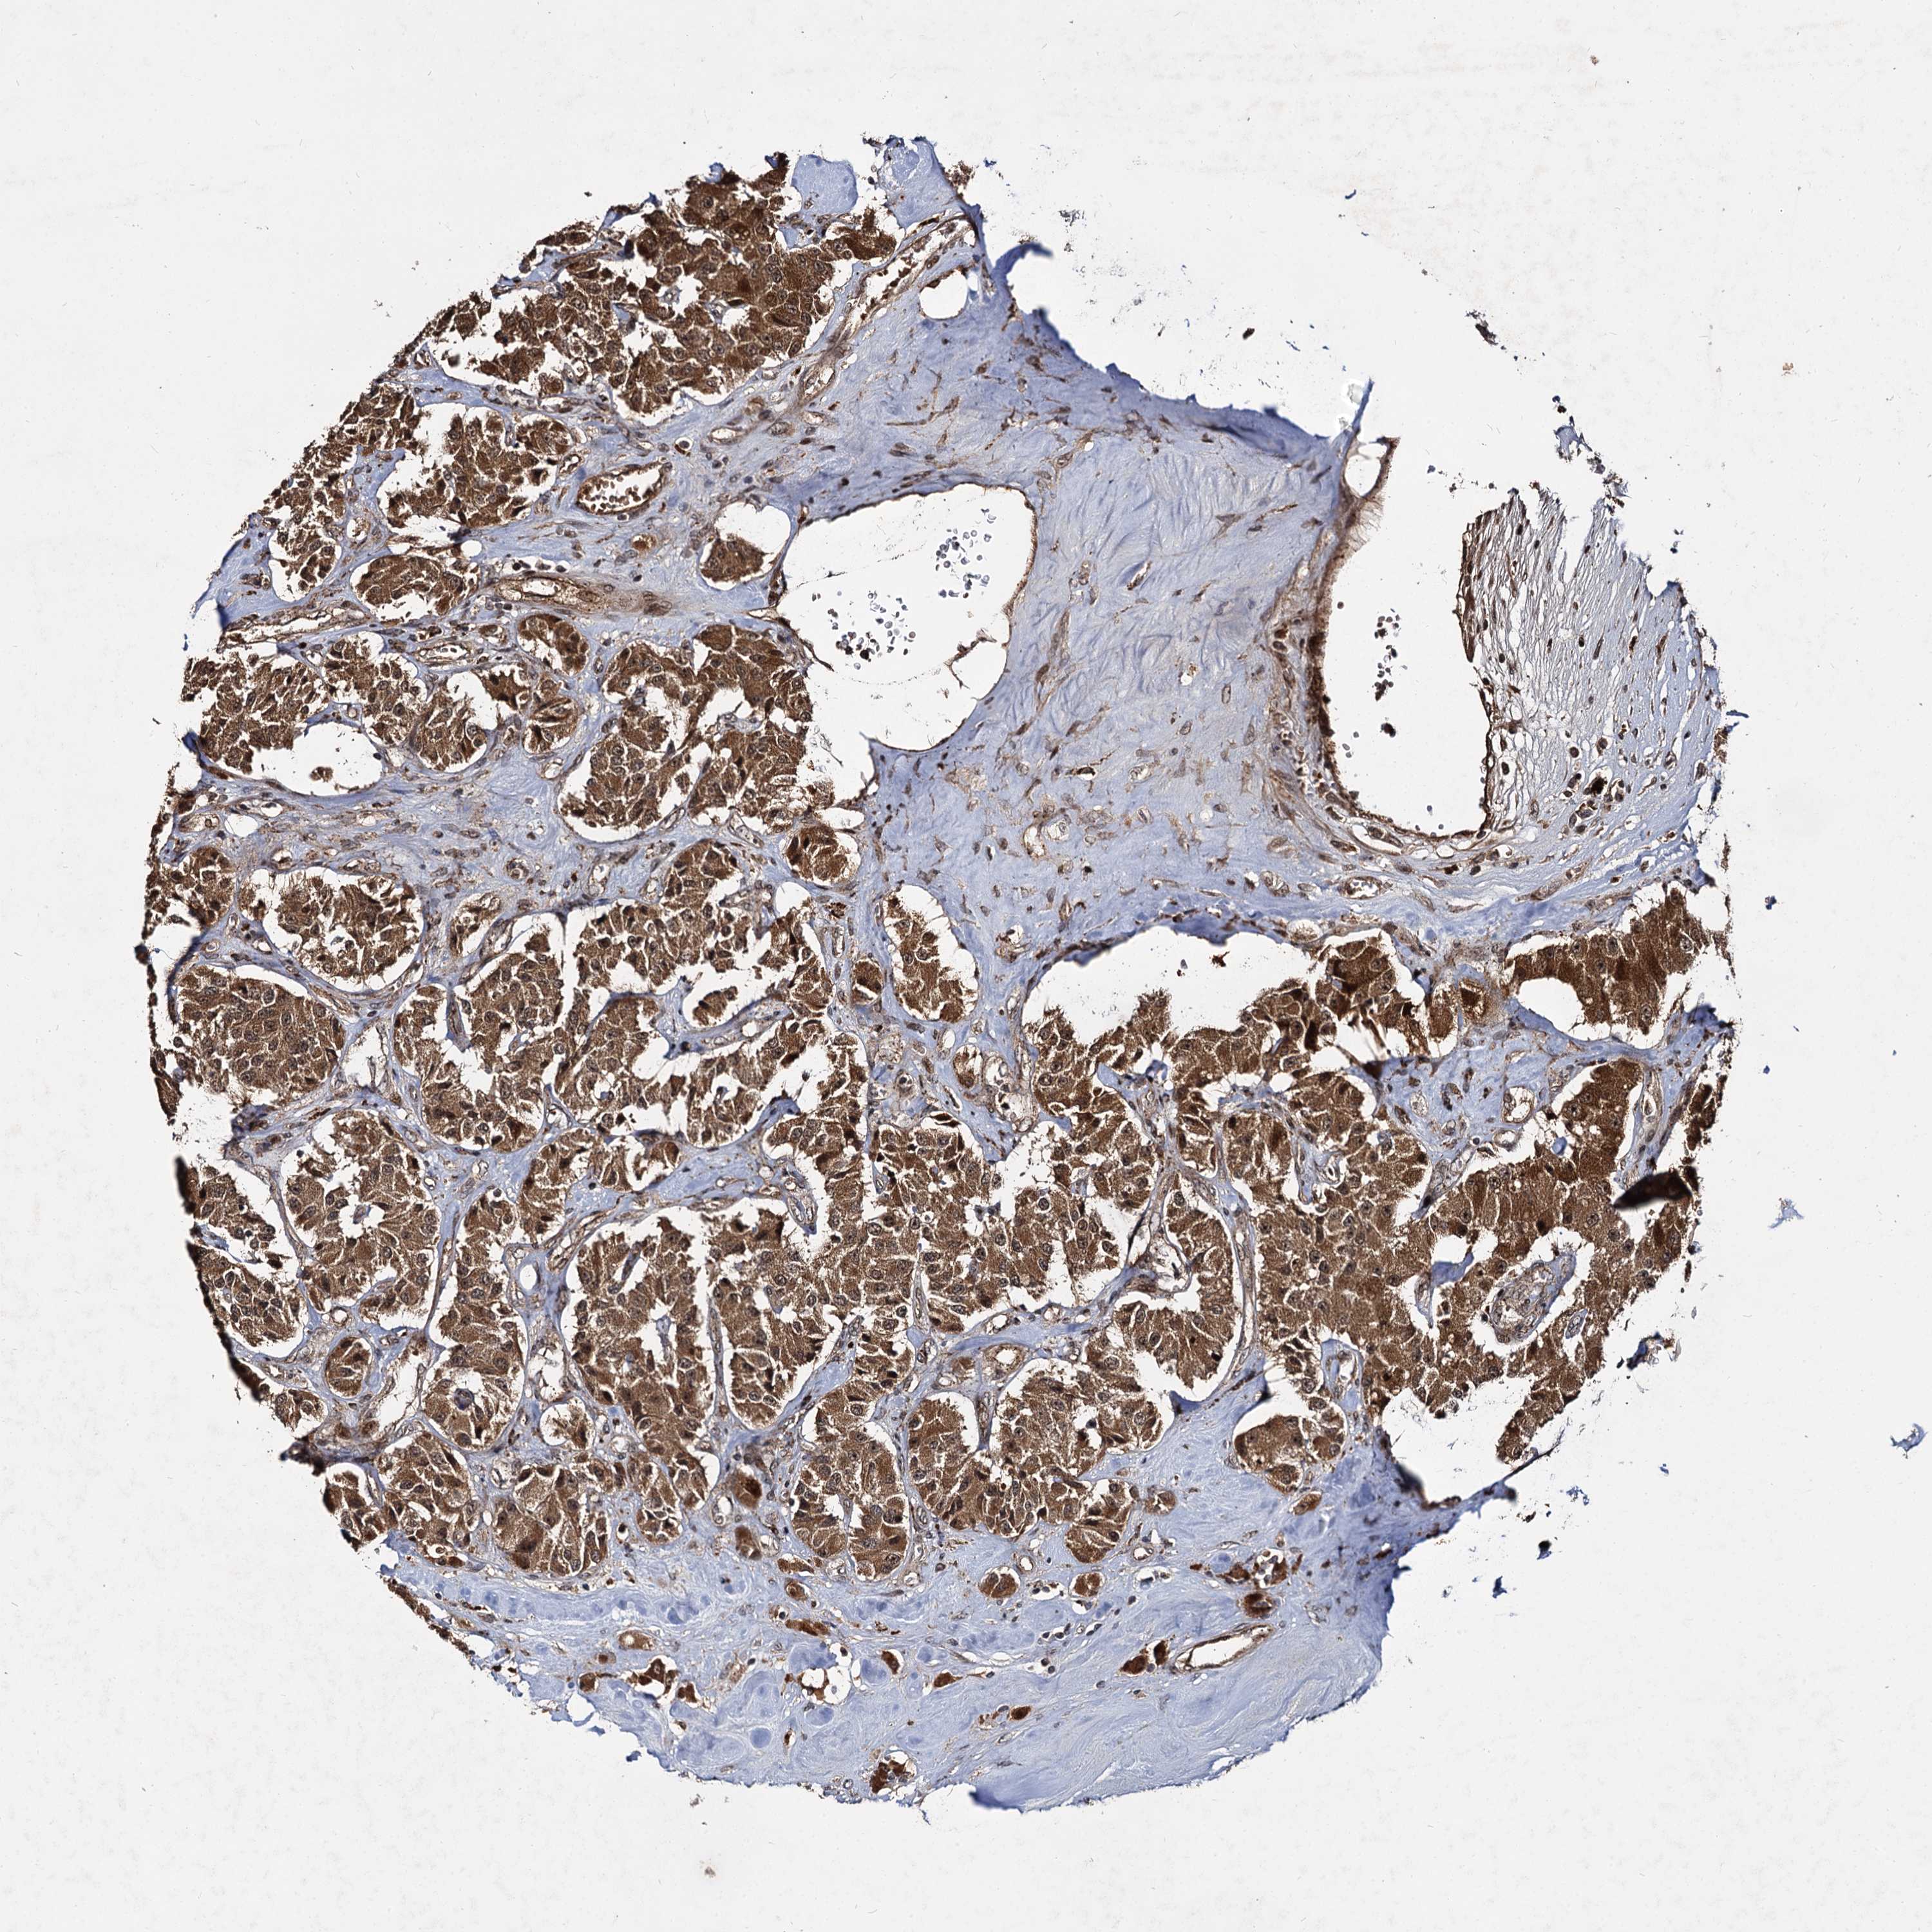

CARCINOID - Protein expressioni

A mouse-over function shows sample information and annotation data. Click on an image to view it in a full screen mode. Samples can be filtered based on level of antibody staining by selecting one or several of the following categories: high, medium, low and not detected. The assay and annotation is described here.

Antibody stainingi

Antibody staining in the annotated cell types in the current human tissue is reported as not detected, low, medium, or high, based on conventional immunohistochemistry profiling in selected tissues. This score is based on the combination of the staining intensity and fraction of stained cells.

Each image is clickable and will lead to virtual microscopy that enables deeper exploration of all samples and also displays staining intensity scores, fraction scores and subcellular localization as well as patient and tissue information for each sample.

Antibody HPA039392

Antibody HPA040503

Staining

High

Medium

Low

Not detected

Intensity

Strong

Moderate

Weak

Negative

Quantity

>75%

75%-25%

<25%

None

Location

Nuclear

Cytoplasmic/membranous

Cytoplasmic/membranous,nuclear

Carcinoid, malignant, NOS

Carcinoma, NOS